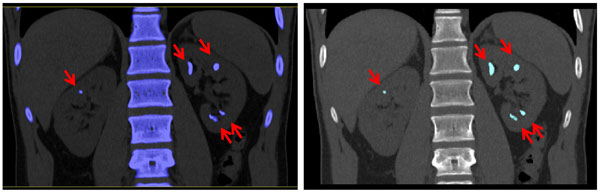

• Image of renal stones

Renal Stone Composition

Dual energy CT can be used to identify specific materials. This is clinically important when the materials look similar using single energy CT. In these non-contrast renal stone exams, the stones (arrows) appear to be comprised of similar materials in the traditional "black and white" images (Left top and bottom).

Dual energy processing can differentiate and "color code" uric acid stones (red) vs. non-uric acid stones (blue) (Right top and bottom).